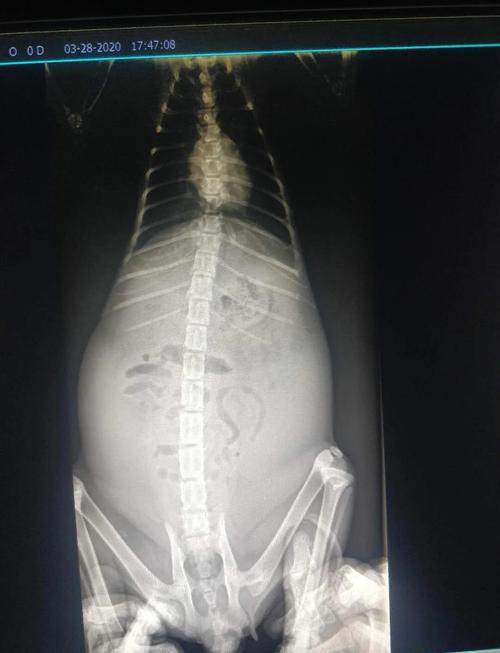

猫咪患慢性肝炎时,通常会出现猫腹水的症状,想要治疗猫慢性肝炎,排肝腹水时必不可少的举措,排除腹水首先应该考虑使用非创伤性的利尿剂来进行。如果利尿剂的排除效果不理想,则再考虑使用其它物理方式来处理。给患猫排除腹水需要循序渐进的进行,不能够一次性全部排尽,以避免腹压发生就大变化致使患咪出现其他并发症。

〖One〗、常伴有淋巴细胞性胆管炎,在猫并不常见。治疗通常是以限制食物中钠的含量和利尿联合治疗,以减少水和钠的潴留。对于限制食物中钠的含量和利尿均无效的病例,可以通过腹腔穿刺抽取腹水,但需要避免一次排出大量腹水,容易导致低血容及肾衰竭。出现了肝腹水的猫咪,建议主人第一时间将猫咪带到医院检查治疗。